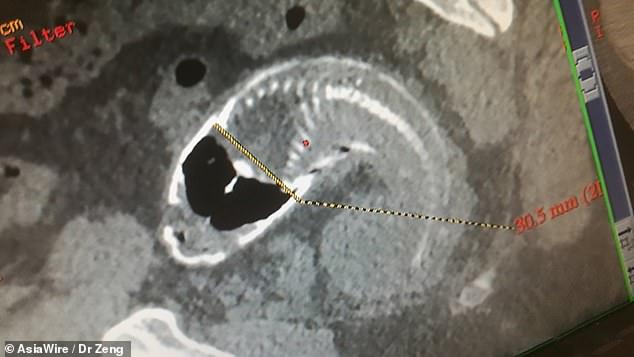

Los médicos hicieron el sorprendente descubrimiento durante una exploración de rayos X después de que el hombre de 30 años fuera al hospital por un dolor abdominal intenso.

Los médicos tuvieron que abrir quirúrgicamente el vientre del hombre para extraer el pez muerto de su recto porque el pez era “bastante grande”.